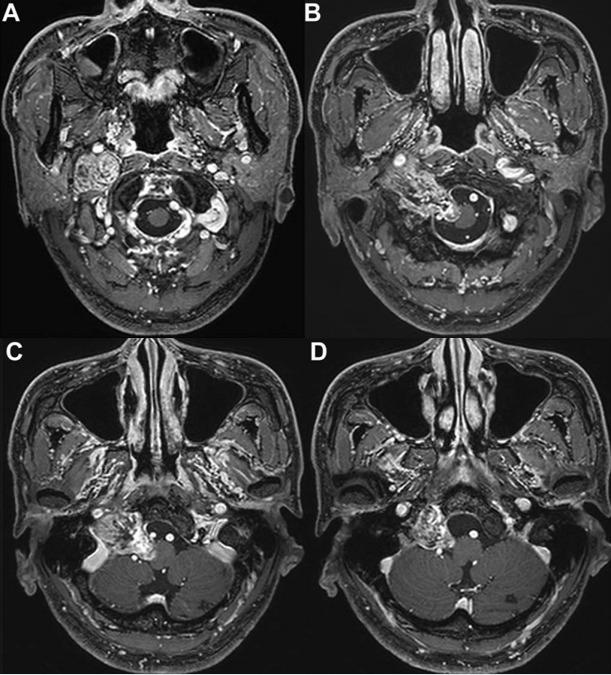

术前MRI

这个被初步诊断为后组颅神经鞘瘤的肿瘤,鉴于肿瘤的囊性成分和大小,手术切除比立体定向放射外科治疗更为合理。肿瘤主要位于颈内动脉(ICA)和颈内静脉之间,位于C1前弓前方,椎前肌外侧;因此,选择前外侧入路(ALA)作为手术方式,术中进行神经电生理监测。